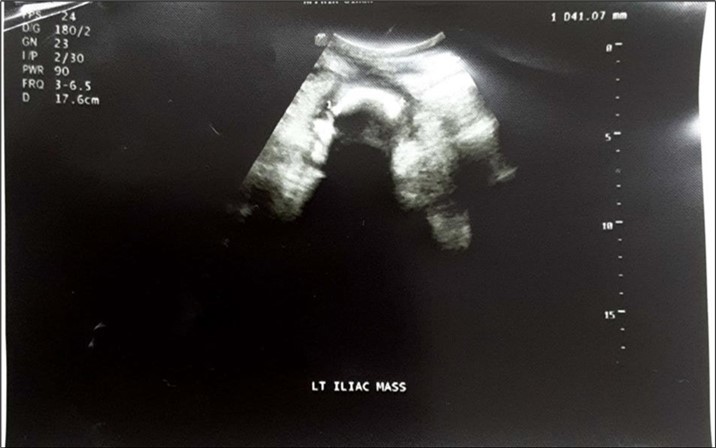

An impression of an intestinal obstruction due to postoperative adhesions was made. An abdominal X-ray done showed no obvious signs of bowel dilatation but an ill-defined opacification in the area of the left lumbar region (Figure 1). An ultrasonography done showed an echogenic mass in the left iliac region measuring about 4.1cm in diameter. There was no flow on colour doppler interrogation (Figure 2). At this point a diagnosis of foreign body was queried. The patient was counselled and prepared for exploratory laparotomy.

Figure 1.Erect abdominal X-Ray showing an ill-defined opacification in the left lumbar region (arrowed).

Erect abdominal X-Ray showing an ill-defined opacification in the left lumbar region (arrowed).

Figure 2.Abdominopelvic USG: An echogenic mass in the left iliac region measuring about 4.1cm in diameter. There was no flow on colour doppler interrogation.

Abdominopelvic USG: An echogenic mass in the left iliac region measuring about 4.1cm in diameter. There was no flow on colour doppler interrogation.